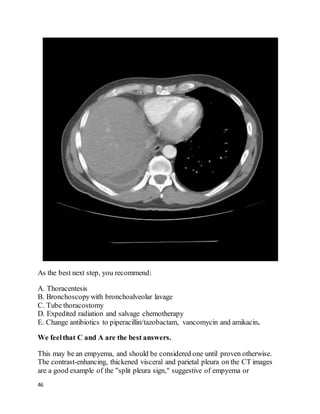

44

45

We feelthat C and A are the best answers.

This may be an empyema, and should be considered one until proven otherwise.

The contrast-enhancing, thickened visceral and parietal pleura on the CT images

are a good example of the "split pleura sign," suggestive of empyema or

Note that the large apparent effusion on scoutchest CT is nearly all due to the

opacity created by an elevated liver/diaphragm due to volume loss after his large

lung resection (see the liver at the level of the heart, on axial cuts). Ultrasound

would help avoid sticking this with a thoracentesis needle. The actual empyema

volume is small. (Cultures of the pleural fluid grew S. pneumoniae). This patient

got a chest tube; these images were actually post-chesttube removal (the original

CT showed an identical-sized fluid collection), which is likely responsible for the

gas bubbles in the effusion.